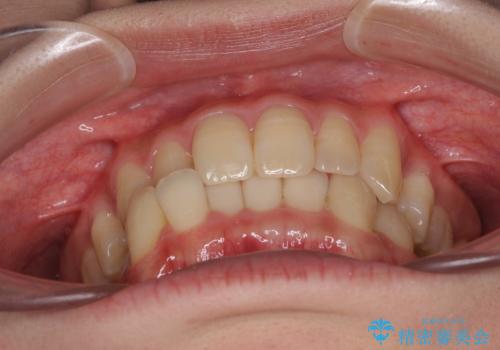

反対咬合が改善され、食いしばり癖もなくなり、顎関節の負担が軽減されました。

上顎骨を拡大したことで前歯に隙間ができ、1ヶ月ほど恥ずかしい時期がありましたが、しっかりとした咬み合わせに仕上がり、患者様には大変満足していただきました。